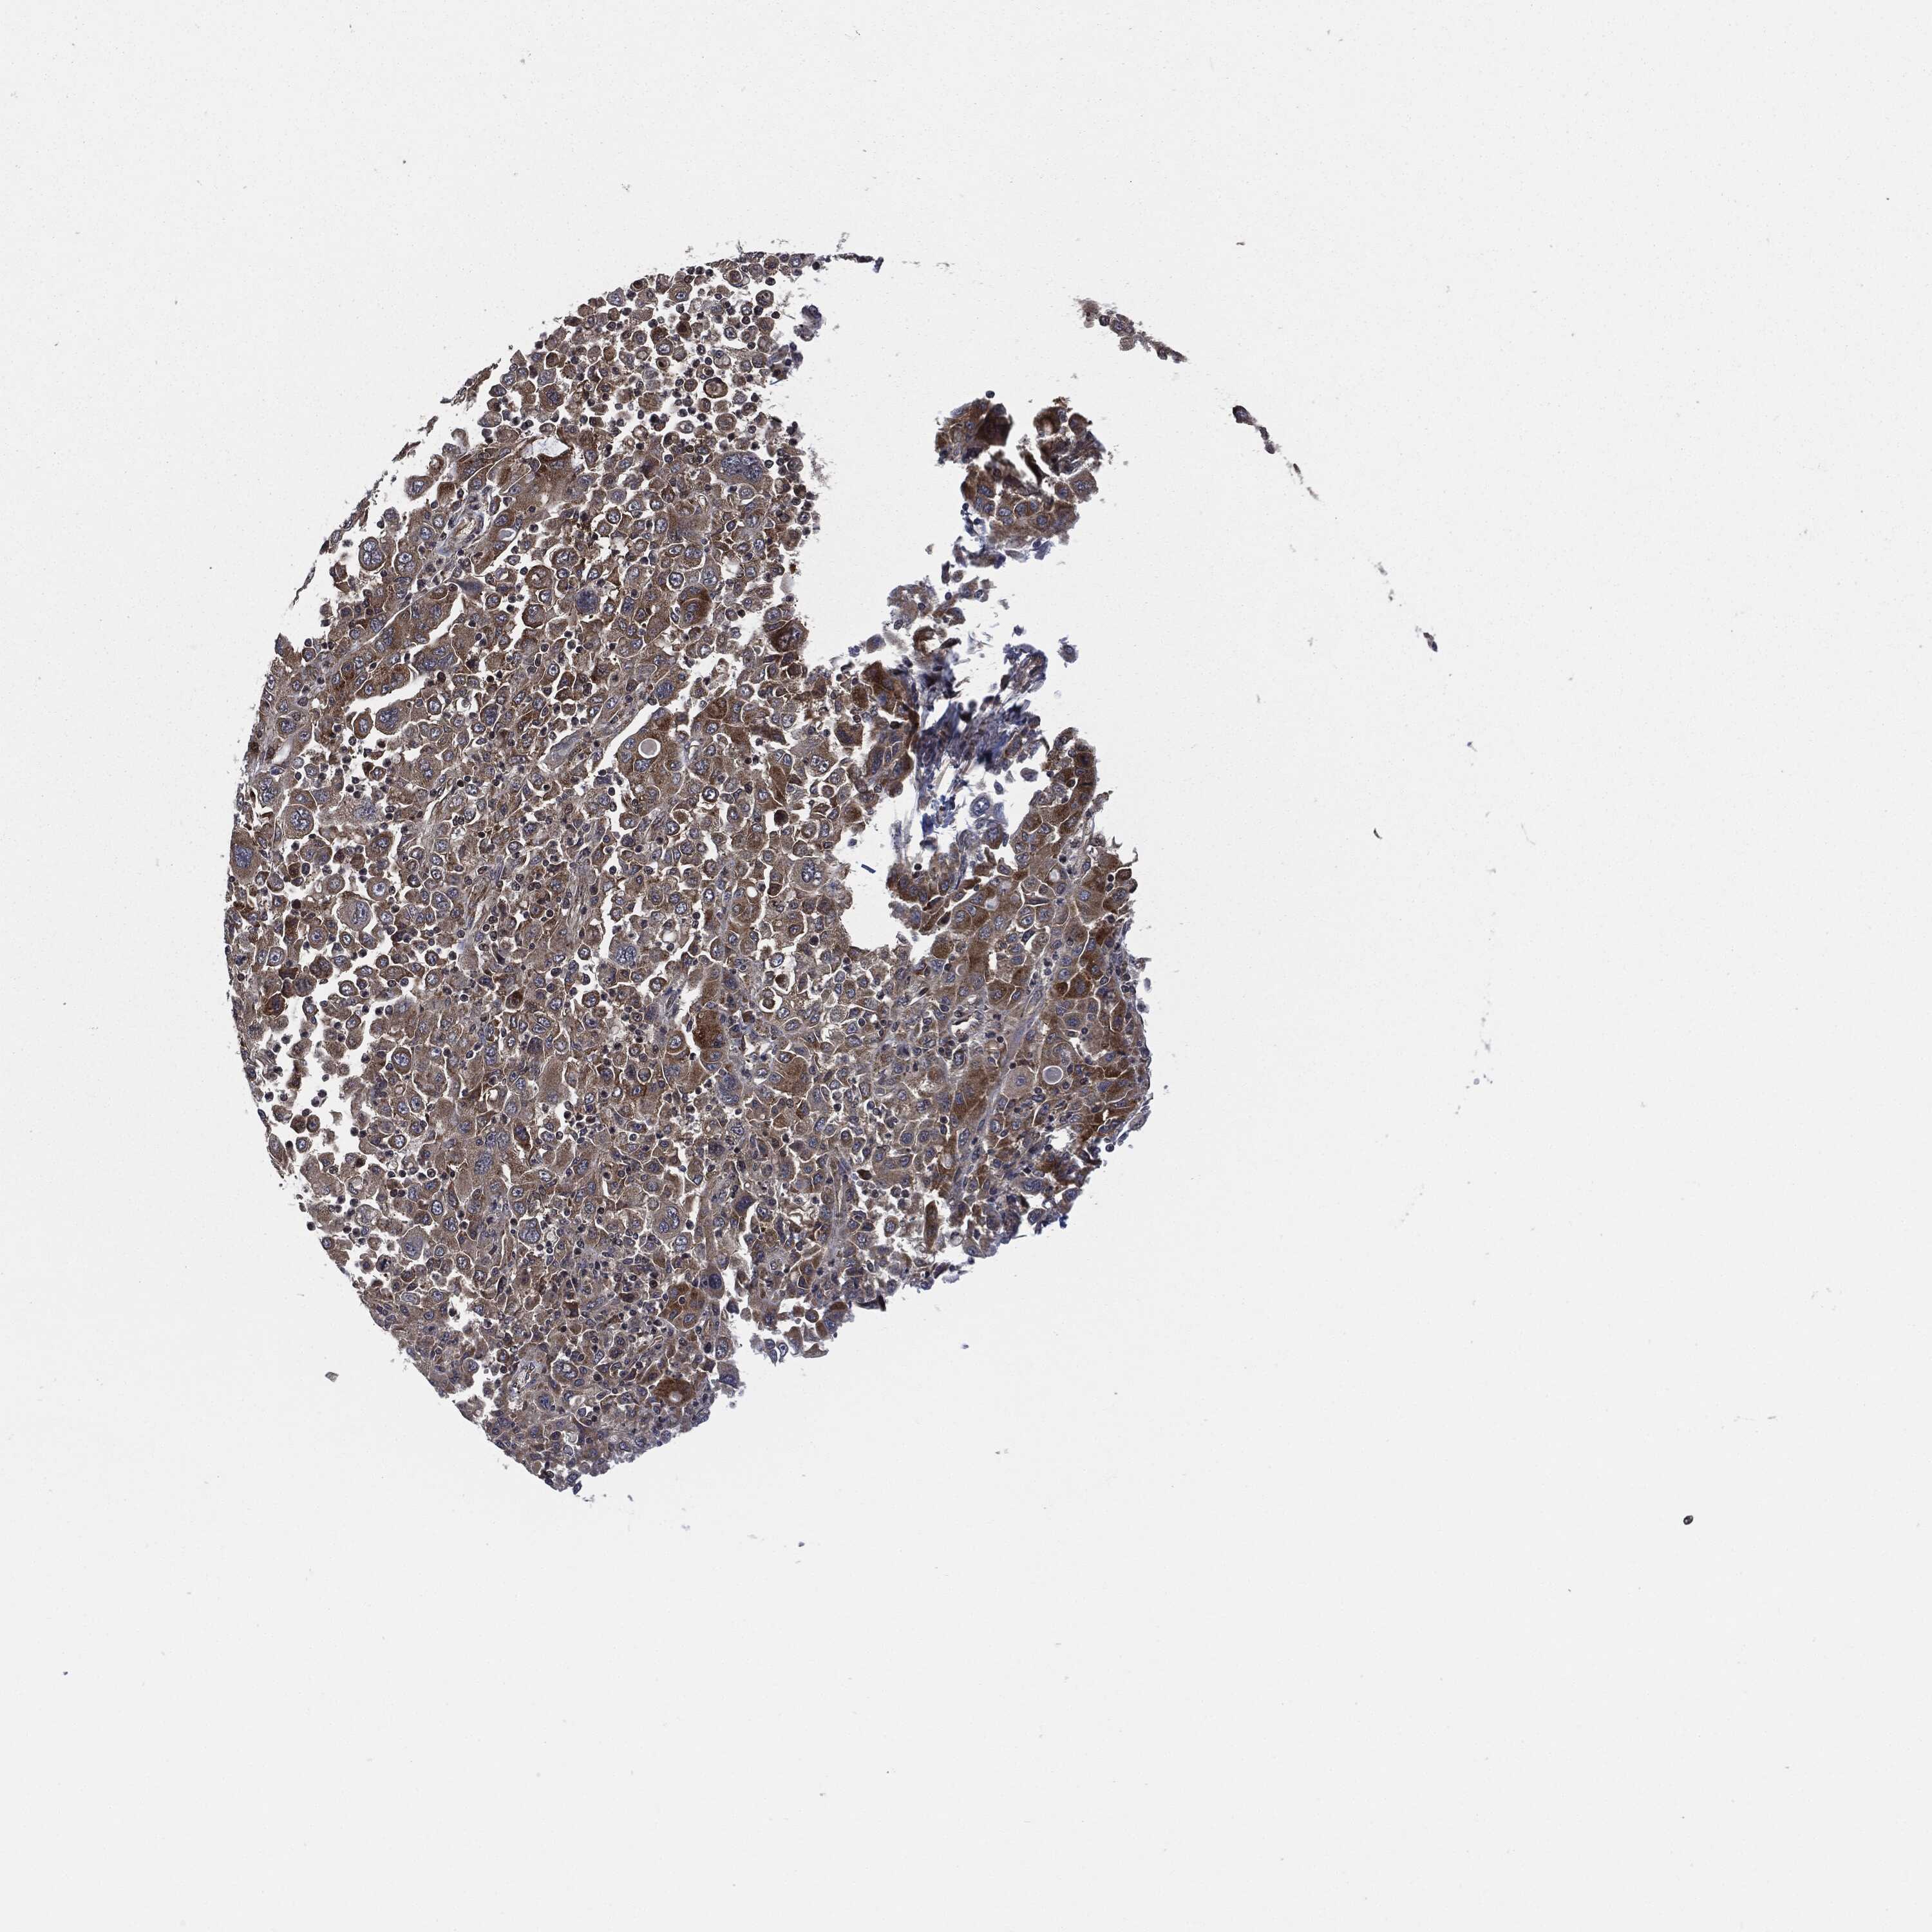

STOMACH CANCER - Protein expressioni

A mouse-over function shows sample information and annotation data. Click on an image to view it in a full screen mode. Samples can be filtered based on level of antibody staining by selecting one or several of the following categories: high, medium, low and not detected. The assay and annotation is described here.

Note that samples used for immunohistochemistry by the Human Protein Atlas do not correspond to samples in the TCGA dataset.

Antibody stainingi

Antibody staining in the annotated cell types in the current human tissue is reported as not detected, low, medium, or high, based on conventional immunohistochemistry profiling in selected tissues. This score is based on the combination of the staining intensity and fraction of stained cells.

Each image is clickable and will lead to virtual microscopy that enables deeper exploration of all samples and also displays staining intensity scores, fraction scores and subcellular localization as well as patient and tissue information for each sample.

HPA049830

CAB002015

CAB080330

CAB080331

CAB080332

Staining

High

Medium

Low

Not detected

Intensity

Strong

Moderate

Weak

Negative

Quantity

>75%

75%-25%

<25%

None

Location

Nuclear

Cytoplasmic/membranous

Cytoplasmic/membranous,nuclear

Adenocarcinoma, NOS

Adenocarcinoma, High grade